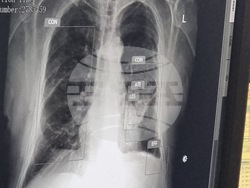

В отделението по образна диагностика на Многопрофилната болница за активно лечение „Рахила Ангелова“ в Перник бе внедрен изкуствен интелект (AI), съобщи пред журналисти директорът на болницата Явор Дренски. Инсталирането на софтуера приключи вчера, а през следващия месец предстои безплатна скринингова кампания за всички жители на областта.

Той посочи, че по време на кампанията изкуственият интелект ще анализира снимките, а при откриване на потенциален проблем ще се включи рентгенолог, който да уточни диагнозата и да насочи пациента за последващо лечение.

Дренски коментира, че AI системата има няколко основни приложения. Освен че подпомага обучението на младите специалисти, тя улеснява работата на рентгенолозите при прецизиране на диагнозата. Софтуерът ще позволява също провеждането на масови скрининги за ранно откриване на заболявания на белия дроб.

„Направата на рентгеновата снимка и разчитането ѝ ще става за минути. Това ще позволи повече хора да се прегледат бързо и ефективно“, допълни директорът на болницата в Перник.